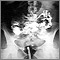

Con un método radiográfico, llamado fluoroscopia, se rastrea la forma como el bario se desplaza a través del esófago, el estómago y el intestino delgado. Se toman imágenes con usted en diferentes posiciones. Puede estar parado o sentado.

El esófago, el estómago y el intestino delgado son normales en tamaño, forma y movimiento.